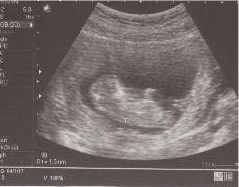

新成員亮相 ( 2007/11/05 )

滿3個月了直到這次正式產檢看到了很具體的寶寶形狀(頭在左邊,大大的身體,可看到小小的手跟腳<i..................